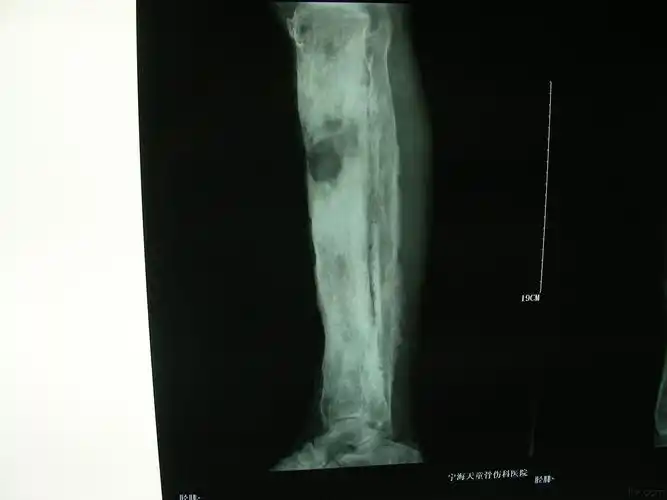

胫骨慢性骨髓炎

这一例胫骨慢性骨髓炎大家有啥好建议